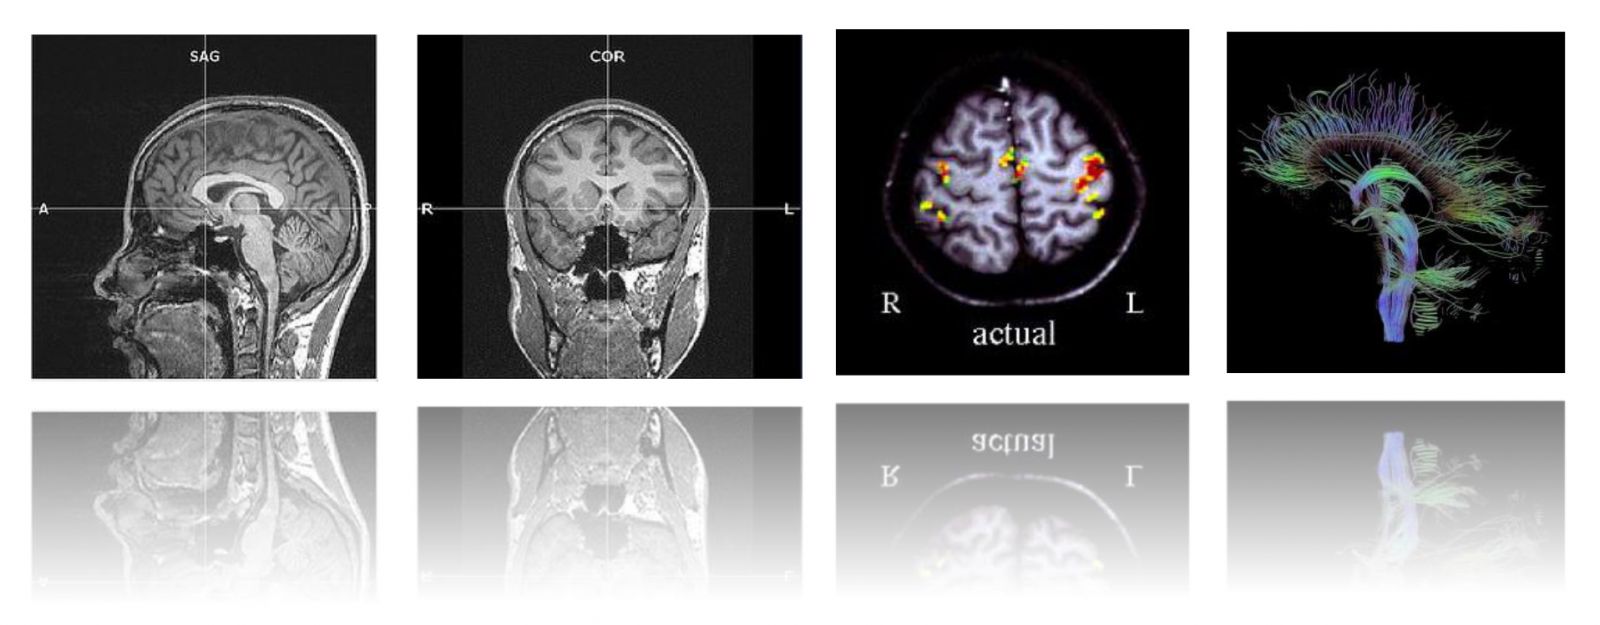

本次工作坊的主題是【影像醫學在精神醫學研究之理論與應用】,我們邀請到影像醫學的專家杜政昊博士 (Dr. CH Tu)陳君明博士 (Dr. CM Chen) ,深入淺出的帶領學員從理論到臨床實務、從操作到研究應用做系統性的授課。課程內容包括形態測量學(VBM)、皮質厚度分析(cortical thickness analysis)和擴散張量影像(DTI)等等。本課程特別優待台灣營養精神醫學研究學會之會員,年底前加入免入會年費!敬請把握!加入會員請點選:連結

這是一個腦科學的研究世代,台灣營養精神醫學研究學會(TSNPR)致力於推動轉譯醫學 (translational medicine) 及跨領域 (interdisciplinary research) 的研究合作。本次工作坊的目的是希望透過系統性的介紹,讓有志從事腦科學研究工作的人員獲得紮實的影像醫學基礎知識,並透過講者的經驗分享,幫助學員掌握此領域的最新研究趨勢。